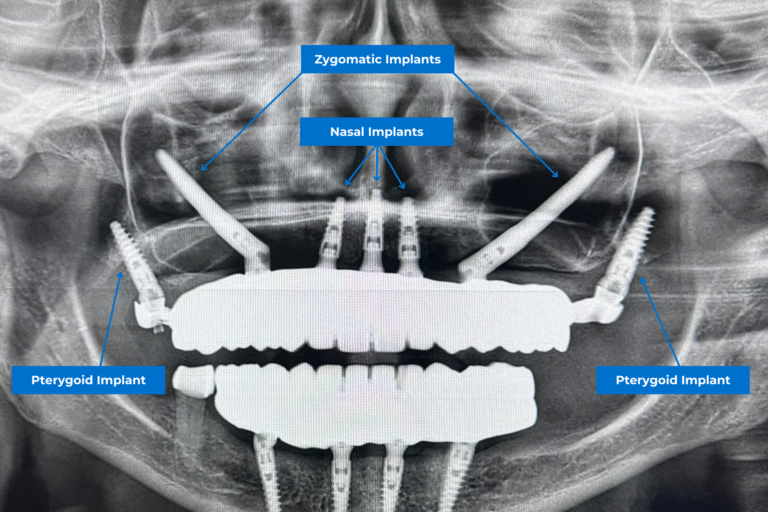

Questi impianti sono tipicamente combinati con impianti zigomatici o convenzionali in una soluzione ibrida full-arch, soprattutto nei trattamenti di tipo All-on-4, per massimizzare il supporto nei casi di estrema atrofia ossea.

Gli impianti nasali come parte di un approccio globale

Mentre gli impianti zigomatici si ancorano allo zigomo e gli impianti pterigoidei nel processo pterigoideo, gli impianti dentali nasali completano queste tecniche fornendo un supporto aggiuntivo attraverso l’osso nasale, in particolare nella regione anteriore della mascella superiore. In alcuni casi, tutti e tre i tipi possono essere combinati per creare una base stabile per i pazienti con una perdita ossea estrema.